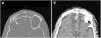

Frontal fracture. (A) Axial computed tomography (CT) with a bone window. Comminuted fracture of the anterior and posterior walls of the frontal sinus with occupation of the same and communication with the anterior cerebral fossa. (B) Axial CT with a brain window. Laminar subdural haematoma and bilateral frontobasal contusive foci.